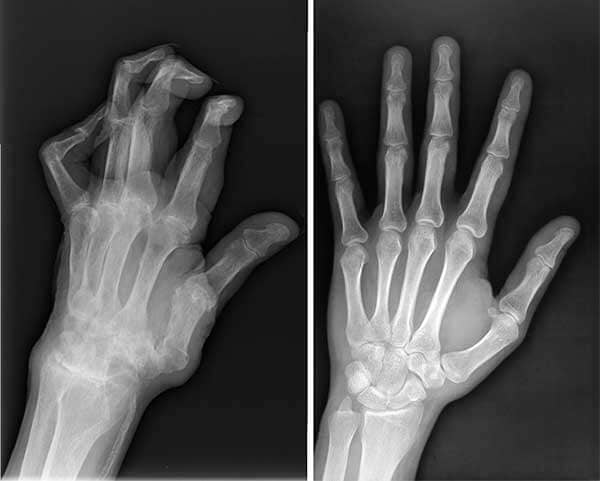

- กิ่งก้านกระดูกสันหลัง ข้อต่อติดแข็ง ก้มลงไม่ได้

- กล้ามเนื้อฝ่อ (จากกระดูกอ่อนข้อต่อเสื่อม ขยับน้อย) เดินยืนเซ

- ข้อต่อผิดรูป รูปร่างเบี้ยว ทั้งปวดและสูญเสียความสวยงาม